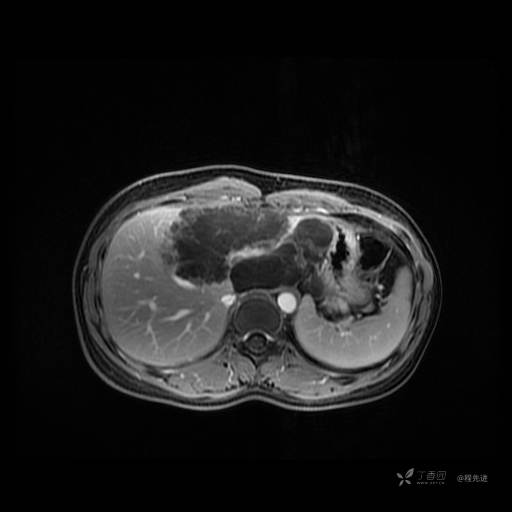

MR平扫+增强

每个序列一张图像(图像太多了,恕不一一发上来)